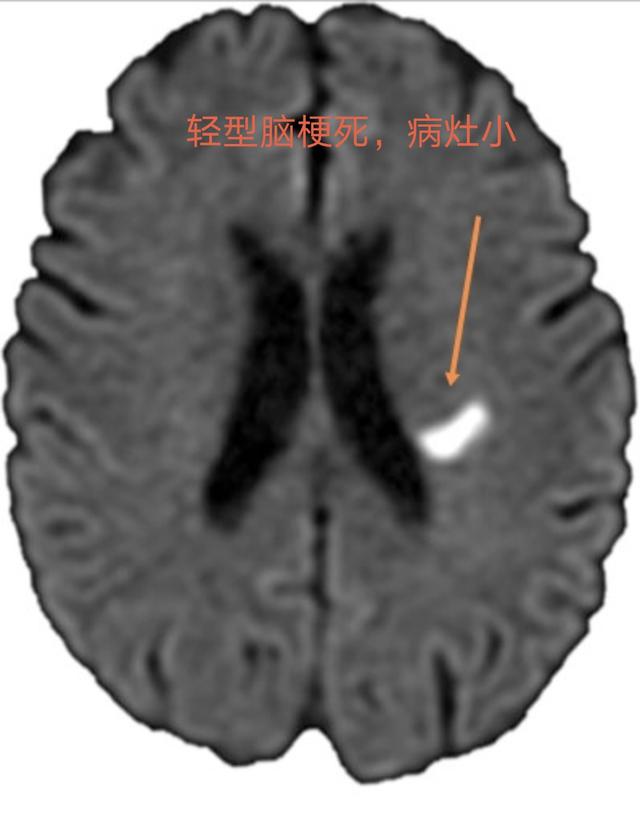

Infarctus cérébral léger ("mini-AVC")Il s'agit d'un dysfonctionnement neurologique léger et focal soudain dû à l'obstruction de petits vaisseaux sanguins.(durée ≥ 24 heures)Les manifestations les plus courantes sontlégère (symptômes, etc.)Faiblesse et engourdissement des membres, discours confus, bouche tordue, troubles de l'équilibre, non accompagnés de troubles de la conscience.La plupart des infarctus sont de petite taille ou situés dans des zones fonctionnelles non motrices, 80 % sont des infarctus lacunaires et la plupart n'entraînent pas d'incapacité significative.Mais elle provoque des lésions permanentes du tissu cérébral.

(3) Il existe une pathologie connue sous le nom d'"infarctus cérébral lacunaire" dans laquelle le patient peutAsymptomatique ou légèrement symptomatiqueLa maladie a été détectée lors d'un examen du cerveau par scanner pour d'autres affections, dont certaines étaient déjà des lésions anciennes.

Étant donné que la durée des symptômes chez les patients souffrant d'un accident ischémique transitoire n'est pas longue, la plupart des patients semblent normaux lorsqu'ils consultent le médecin, mais ils devraient également améliorer les examens tels que la tomodensitométrie crânienne ou l'imagerie par résonance magnétique. Si l'examen d'imagerie ne révèle aucune lésion d'infarctus cérébral, le diagnostic d'accident ischémique transitoire devrait être posé et, en même temps, une hémorragie cérébrale peut être exclue, car elle peut également présenter des symptômes similaires. À ce stade, bien que les symptômes aient été soulagés, cela ne signifie pas qu'aucun autre diagnostic et traitement n'est nécessaire, et il est encore nécessaire d'améliorer l'angiographie par tomodensitométrie, l'angiographie par résonance magnétique ou l'angiographie, etc., pour clarifier la gravité des lésions vasculaires dans la tête et le cou, afin de guider l'élaboration d'un plan de traitement raisonnable.Il est important de noter queAu stade précoce de l'infarctus cérébral, les foyers d'infarctus cérébral ne peuvent être détectés par le scanner ou l'IRM, et la durée maximale d'un accident ischémique transitoire est de 24 heures ; comment différencier un accident ischémique transitoire d'un infarctus cérébral au cours de cette période de 24 heures ? La résonance magnétique pondérée en diffusion permet de détecter les premiers foyers d'infarctus cérébral.